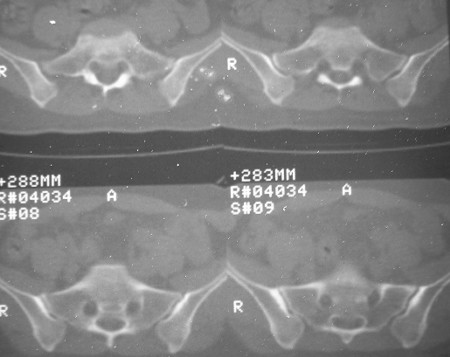

标题: CT7246: F,30岁,下腰痛,同事的片子,请老师们看看,初 [打印本页]

标题: CT7246: F,30岁,下腰痛,同事的片子,请老师们看看,初

典型的致密性髂骨炎

典型的双侧骶髂关节致密性骨炎.

何谓髂骨致密性骨炎?髂骨致密性骨炎是发生于髂骨耳状关节部分的骨质密度增高性疾病。病因迄今不明,可能与妊娠、机械性劳损、病灶性炎症有关。本病好发于20~35岁的育龄妇女,偶见男性。

髂骨致密性骨炎的临床表现与体征:腰骶部疼痛,多呈慢性、间歇性酸痛、隐痛,可向一侧或双侧臀部及大腿后侧扩散,但不沿坐骨神经方向放射,步行、站立、负重及劳累后加重,咳嗽、打喷嚏不能使疼痛明显加重,休息后症状减轻。患者腰骶角加大,局部有压痛和肌紧张,骨盆分离和挤压试验阳性,“4”字试验阳性,化验检查多在正常范围内。x线检查,骶髂关节间隙整齐清晰,靠近骶髂关节面中的髂骨耳状关节部分骨质密度增高,呈均匀浓白边缘清晰的骨质致密带,骨小梁消失,无骨质破坏。本病应注意与早期强直性脊柱炎、骶髂关节结核相鉴别。